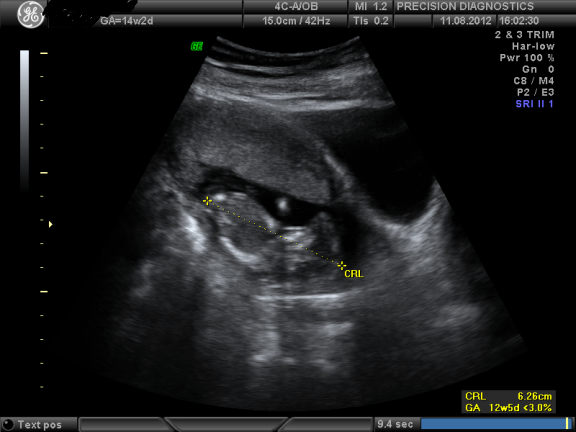

baby at 14 weeks 2 days ultrasound

14 weeks pregnant bellies. 14 week Ultrasound can be performed Transabdominally or Transvaginally and here is what a normal 14 week baby ultrasound should look like. Find out whats going on during this exciting stage of pregnancy.

Crown-rump length or CRL is. A 6 week developing fetus is very small but you should see the gestational sac on a normal 6 week ultrasound black fluid on ultrasound and the yolk sac the little white ring.